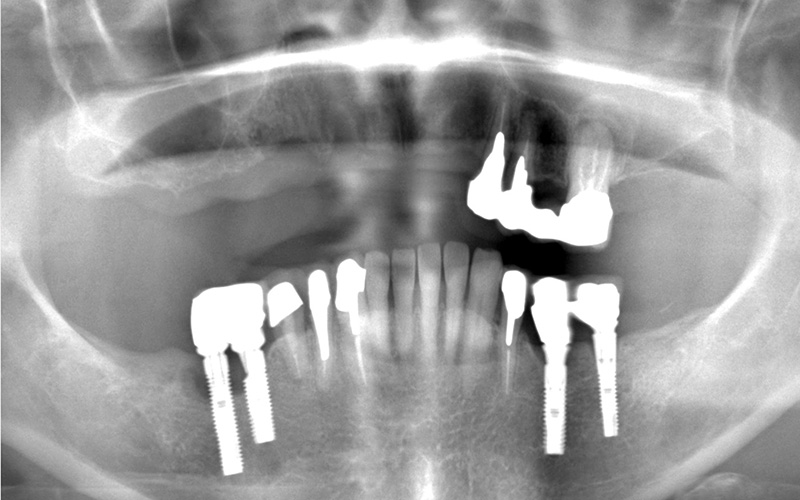

右側上顎洞にサイナスリフト処置を行い、同日にインプラント体を2本の埋入。2か月後に左右前歯部にインプラント体のを4本埋入。インプラントと骨が結合したのを確認後、仮歯の装着を行い、咬合の安定を図り、最終補綴処置をジルコニア性上部構造物にて作成を行い装着。

診断結果 レントゲンで見ると、既存骨が菲薄化しており、上顎洞との距離が短く、インプラントを入れる骨のスペースが少ないことが認めた。左右前歯部の残存している骨は良好であった。

治療前の画像

治療中の画像